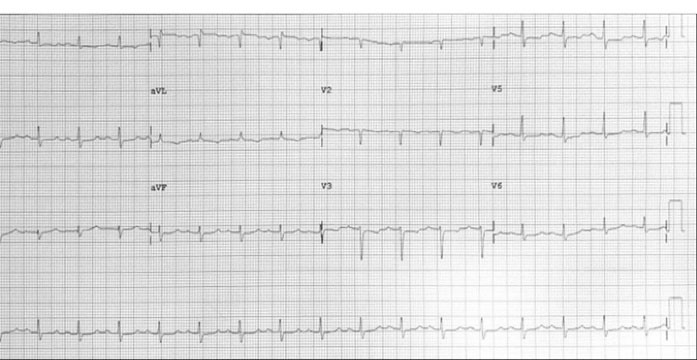

A 57-year-old lady with history of rheumatic mitral valve disease underwent mitral valve replacement by Saint Jude Medical Epic bioprosthesis in our high-volume mitral surgery center. Preoperative coronary angiography was non-significant except for a moderate stenosis of mid left anterior descending artery (LAD) (). The patient underwent coronary artery bypass grafting (CABG) using left internal mammary artery (LIMA) to LAD concomitantly with mitral valve surgery. The surgery was smooth with no postoperative complications. On serial postoperative electrocardiogram (EKG), there was no ST segment elevation or new significant ischemic changes compared to preoperative EKG. Routine postoperative echocardiogram showed good function of the mitral prosthesis and good global function of the left ventricle. Four weeks later, the patient started to have dyspnea, orthopnea and other symptoms of heart failure. EKG showed non-significant ST-T changes (). Echocardiography showed severely impaired left ventricle (LV) systolic function. Moreover, there was a localized hematoma adjacent to the right atrium without hemodynamic impact (). In light of these findings along with elevated troponin level, we decided to repeat coronary angiography. The later showed complete occlusion of the proximal LCX () and stenosis of the LIMA -LAD anastomosis. A PCI strategy was successful for LIMA-LAD stenosis () but difficult for LCX lesion; after crossing the lesion using work-horse wire, and use of different size non-compliant and compliant balloons, there was continuous recoil after balloon deflation (). The trial of angioplasty and stenting was failed with no recuperation of distal flow. Therefore, we suspected surgical complication with mechanical compression of the circumflex coronary artery most probably by encircling suture loop, in addition to stenosis of the LIMA-LAD. Furthermore, the retro atrial hematoma might be caused by epicardial coronary artery injury. The procedure was then stopped and the patient was kept on medical treatment. On follow up visits, there was complete resolution of the atrial hematoma, and a significant improvement of LV function on standard heart failure treatment.

Figure 3. EKG four weeks later showed non specific ST-T changes.